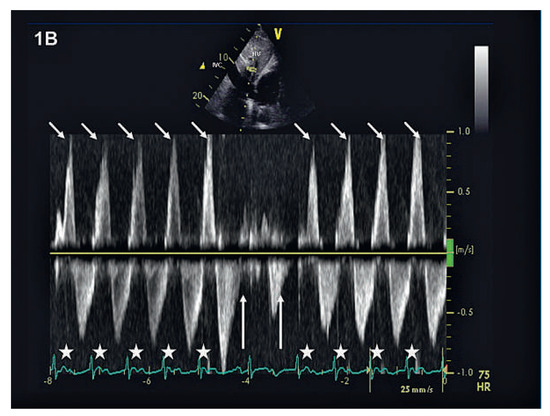

A 59-year-old man with severe mitral regurgitation underwent successful mitral valve repair. Postoperative recovery was uneventful except for the development of a third-degree atrio-ventricular block (fig. 1A). The haemodynamic consequences of the atrio-ventricular dissociation were observed during echocardiography (fig. 1B and fig. 1C): at the beginning and the end of the re- cordings, right atrial depolarisation and contraction occurs during ventricular systole when the tricuspid valve is closed, leading to reversal of blood flow (short arrows). This echocardiographic finding represents the clinically observable jugular venous pulsation called “Cannon waves”. In contrast, when the atrio-ventricular sequence is more or less correct, the backflow into the IVC and the HV is minimal (long arrows).

Figure 1B. Pulse-wave Doppler through a hepatic vein demonstrating blood flow reversals during atrioventricular block. If atrioventricular sequence is correct (arrows), backflow into the hepatic vein is minimal.